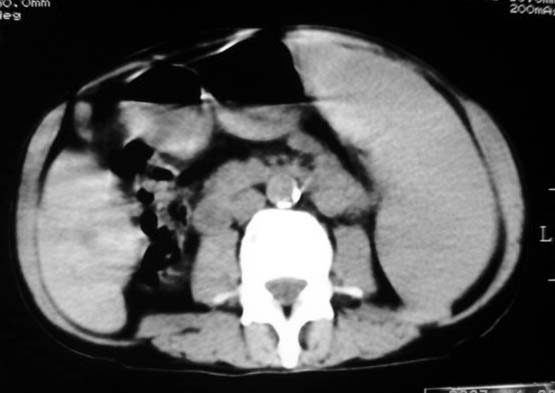

以下是引用dyqct在2007-4-20 16:38:00的发言:[br]考虑:1、巨脾;[br] 2、肝内多发低密度,首先考虑转移瘤;[br] 3、胆囊多发结石。

以下是引用andymaomao在2007-4-20 16:47:00的发言:[br]肝脾增大,肝内胆管扩张,且可见多发小囊性低密度灶,胆囊窝区高密度影,手术化疗病史,贫血....[br]1.肝脾大及贫血与术后化、药疗有关;[br]2.胆囊窝区高密度影,术后改变?肝内胆管扩张,积液?[br]3.肝内多发低密度灶,性质?建交增强